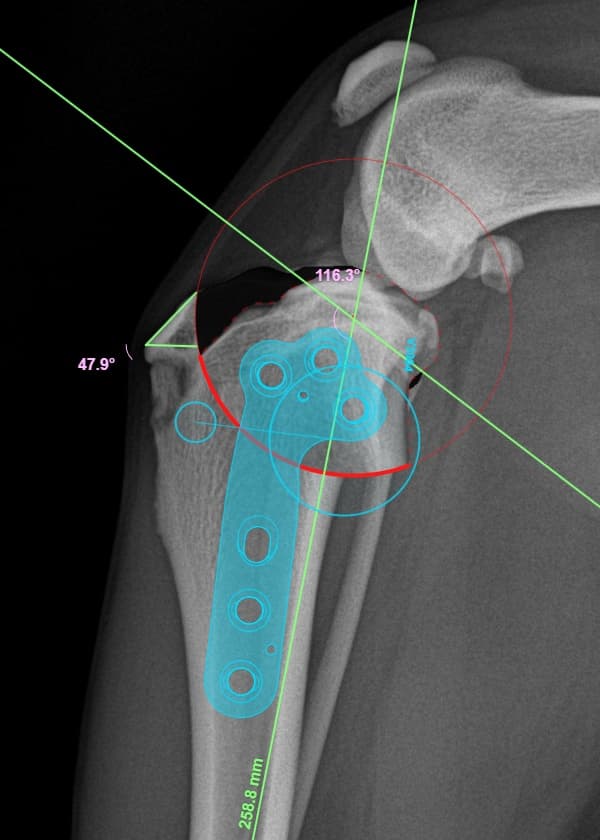

정형외과 전공의 수의사가 직접 수술합니다.

02C-arm을 통해서 좀 더 섬세한 정형외과 수술을 진행하고, 본원에서는 외과적 침습을 최소화 하는 중재적 시술 (기관 협착, 동맥관개존증(PDA), SUB 등)을 진행하고 있습니다.

12정교한 정형외과 도구를 사용하여 신속 정확한 정형외과 수술이 가능

13수술 중 골절 상태 혹은 이식물 적용 후 상태 등 육안으로 명확히 확인하기 힘든 상태를 X-ray 확인하여 정확한 수술 결과를 만들어 내는 것이 가능